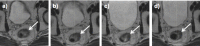

CT-based radiotherapy workflow is limited by poor soft tissue definition in the pelvis and reliance on rigid registration methods. Current image-guided radiotherapy and adaptive radiotherapy models therefore have limited ability to improve clinical outcomes. The advent of MRI-guided radiotherapy solutions provides the opportunity to overcome these limitations with the potential to deliver online real-time MRI-based plan adaptation on a daily basis, a true "plan of the day." This review describes the application of MRI guided radiotherapy in two pelvic tumour sites likely to benefit from this approach.